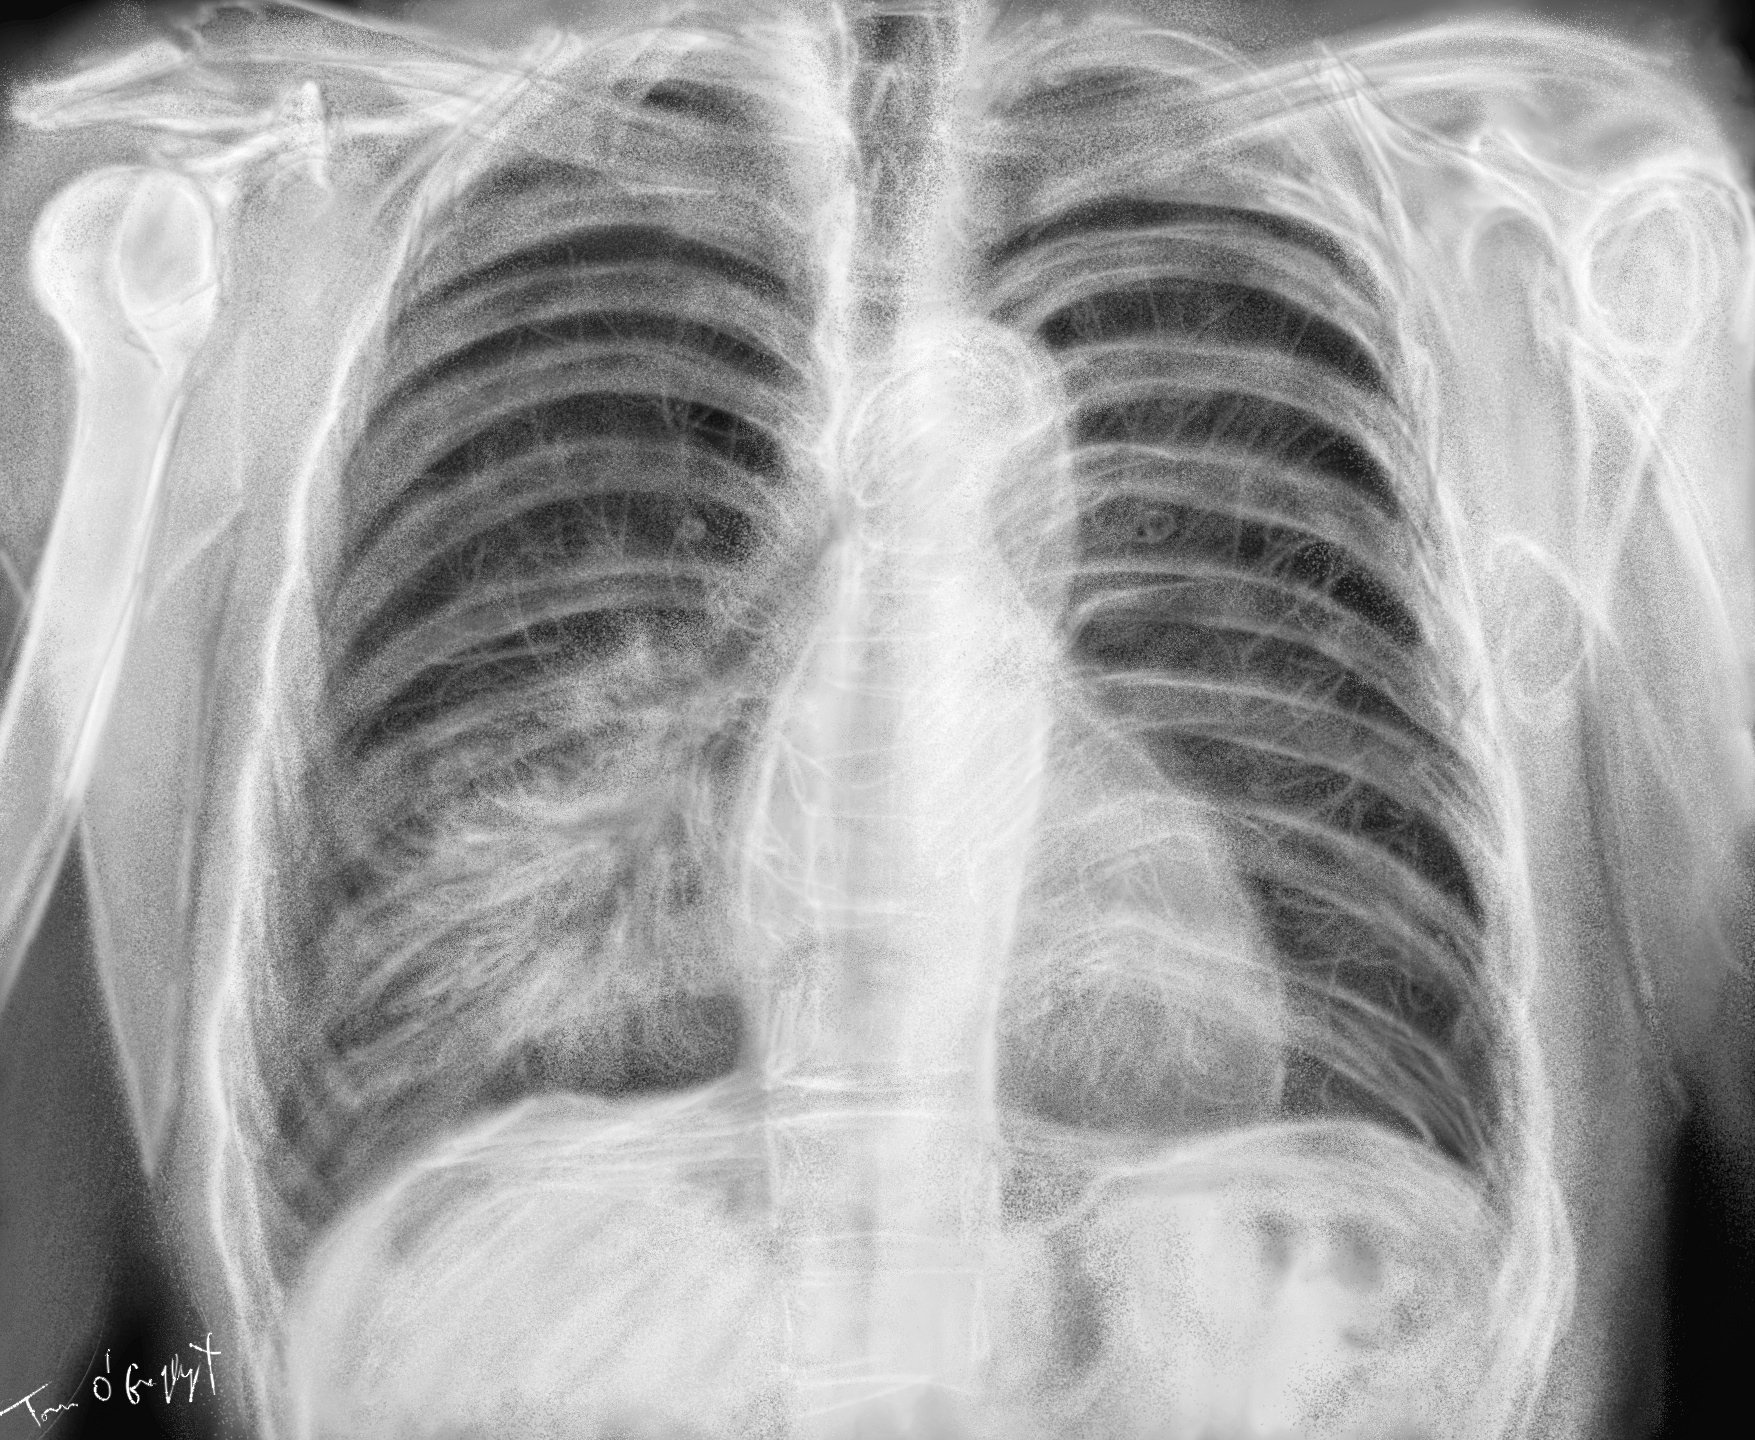

L’imagerie souvent réalisée est utile pour la détection de pneumopathies et identifier les complications mais ne donne que rarement des indications pour l’identification du germe. Deux présentations d’imagerie sont possibles : la condensation alvéolaire (uni ou bilatérale) et le syndrome interstitiel.

Elle est utile pour voir le foyer d’infection sous forme d’un infiltrat radio-opaque assez bien systématisé en cas de PFLA. Elle visualise facilement aussi un épanchement pleural parapneumonique associé (la moitié dans les cas de pneumonie à Haemophilus).

Dans la pneumonie lobaire, focale ou non-segmentaire, on peut voir la consolidation homogène intéressant un ou plusieurs lobes, avec persistance d’une bronche large ouverte et d’un bronchogramme aérique. Elle résulte de l’évolution rapide en œdème avec peu de réaction cellulaire survenant d’abord en périphérie et s’étendant ensuite entre les acini à travers les pores de Kohn et les canaux de Lambert.

Lors de l’infection caractérisée à pneumocoque, on peut voir une opacité parenchymateuse homogène lobaire avec bronchogramme aérique

et prenant à l’occasion l’aspect d’une masse arrondie.

pneumonie lobaire inférieure gauche assez discrète en radiographie mais du fait d’un foyer rétrocardiaque

La bronchopneumonie ou pneumonie multifocale ou lobulaire, est visualisée radiologiquement par un aspect irrégulier avec épaississement péribronchique et une mauvaise délimitation air-opacités. À mesure que l’infection devient plus sévère, la consolidation impliquant les bronchioles terminales et les alvéoles entraine des opacités centrolobulaires nodulaires. Elles peuvent ensuite fusionner pour donner un aspect lobaire, et au maximum une image de poumon blanc, qui, en radiographie peut faire hésiter avec une pleurésie complète dans la grande cavité. À la différence de celle-ci, il n’y a pas de refoulement du médiastin du côté opposé, ni de la trachée mais plutôt une attraction de celle-ci du côté malade.